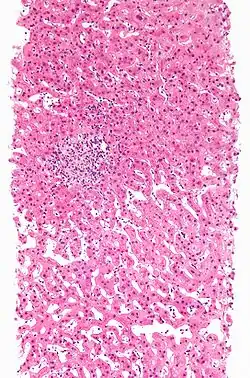

L'hépatotoxicité est considérée comme le pouvoir qu'a une substance de provoquer des dommages au foie[1],[2] ; cela intervient généralement à la suite de la prise de médicaments.